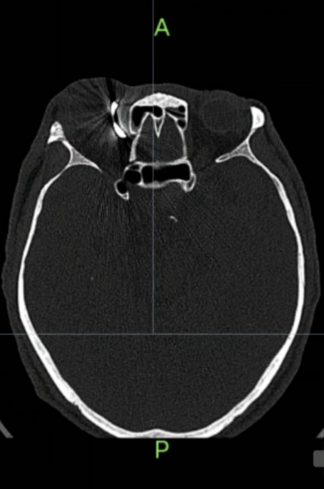

眼眶CT

眼科医学诊疗中心主治医师刘晓弟接诊后发现王先生右眼上眼睑有些红肿,眉头下方有一个米粒大小的伤口,并未看见异物的踪影。完善相关检查后,发现刘先生右侧眼眶内有一直径约为2厘米的弧形钉状致密影。